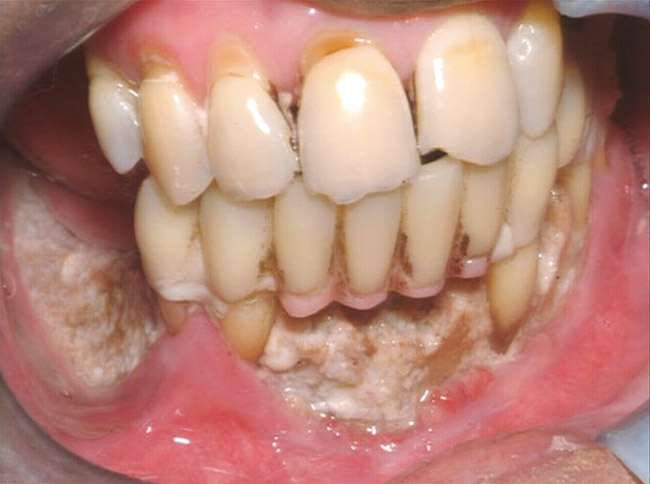

Then, patient was able to move forward with the prosthesis. Figure 10 shows a periodontal patient who was taking oral bisphosphonates for osteoporosis. The patient had full-mouth scaling and root planing, then was given 2 months to heal and instructed to rinse with chlorhexidine twice daily. After no signs of BRONJ were observed, the patient had full-mouth osseous surgery on her few remaining teeth in the mandible. The surgery was performed all at once and not according to the sextant approach because the patient was on a heart and lung transplant list and was moved up the list while healing from the scaling and root planing. The patient also had extensive bone loss in her anterior mandible (Figure 11).To avoid performing extractions, a simple composite splint was placed between the partial dentures (Figure 12 and Figure 13). The splint reduced the mobility of the teeth and made them less likely to be knocked out during any surgical intubation procedure.

Figure 10  Patient who takes oral bisphosphonates and suffers from periodontal diseas.

Figure 10

Figure 11  The radiograph shows 80% bone loss.

Figure 11

Figure 12  Facial view of composite splint.

Figure 12

Figure 13  Occlusal view of composite splint.

Figure 13